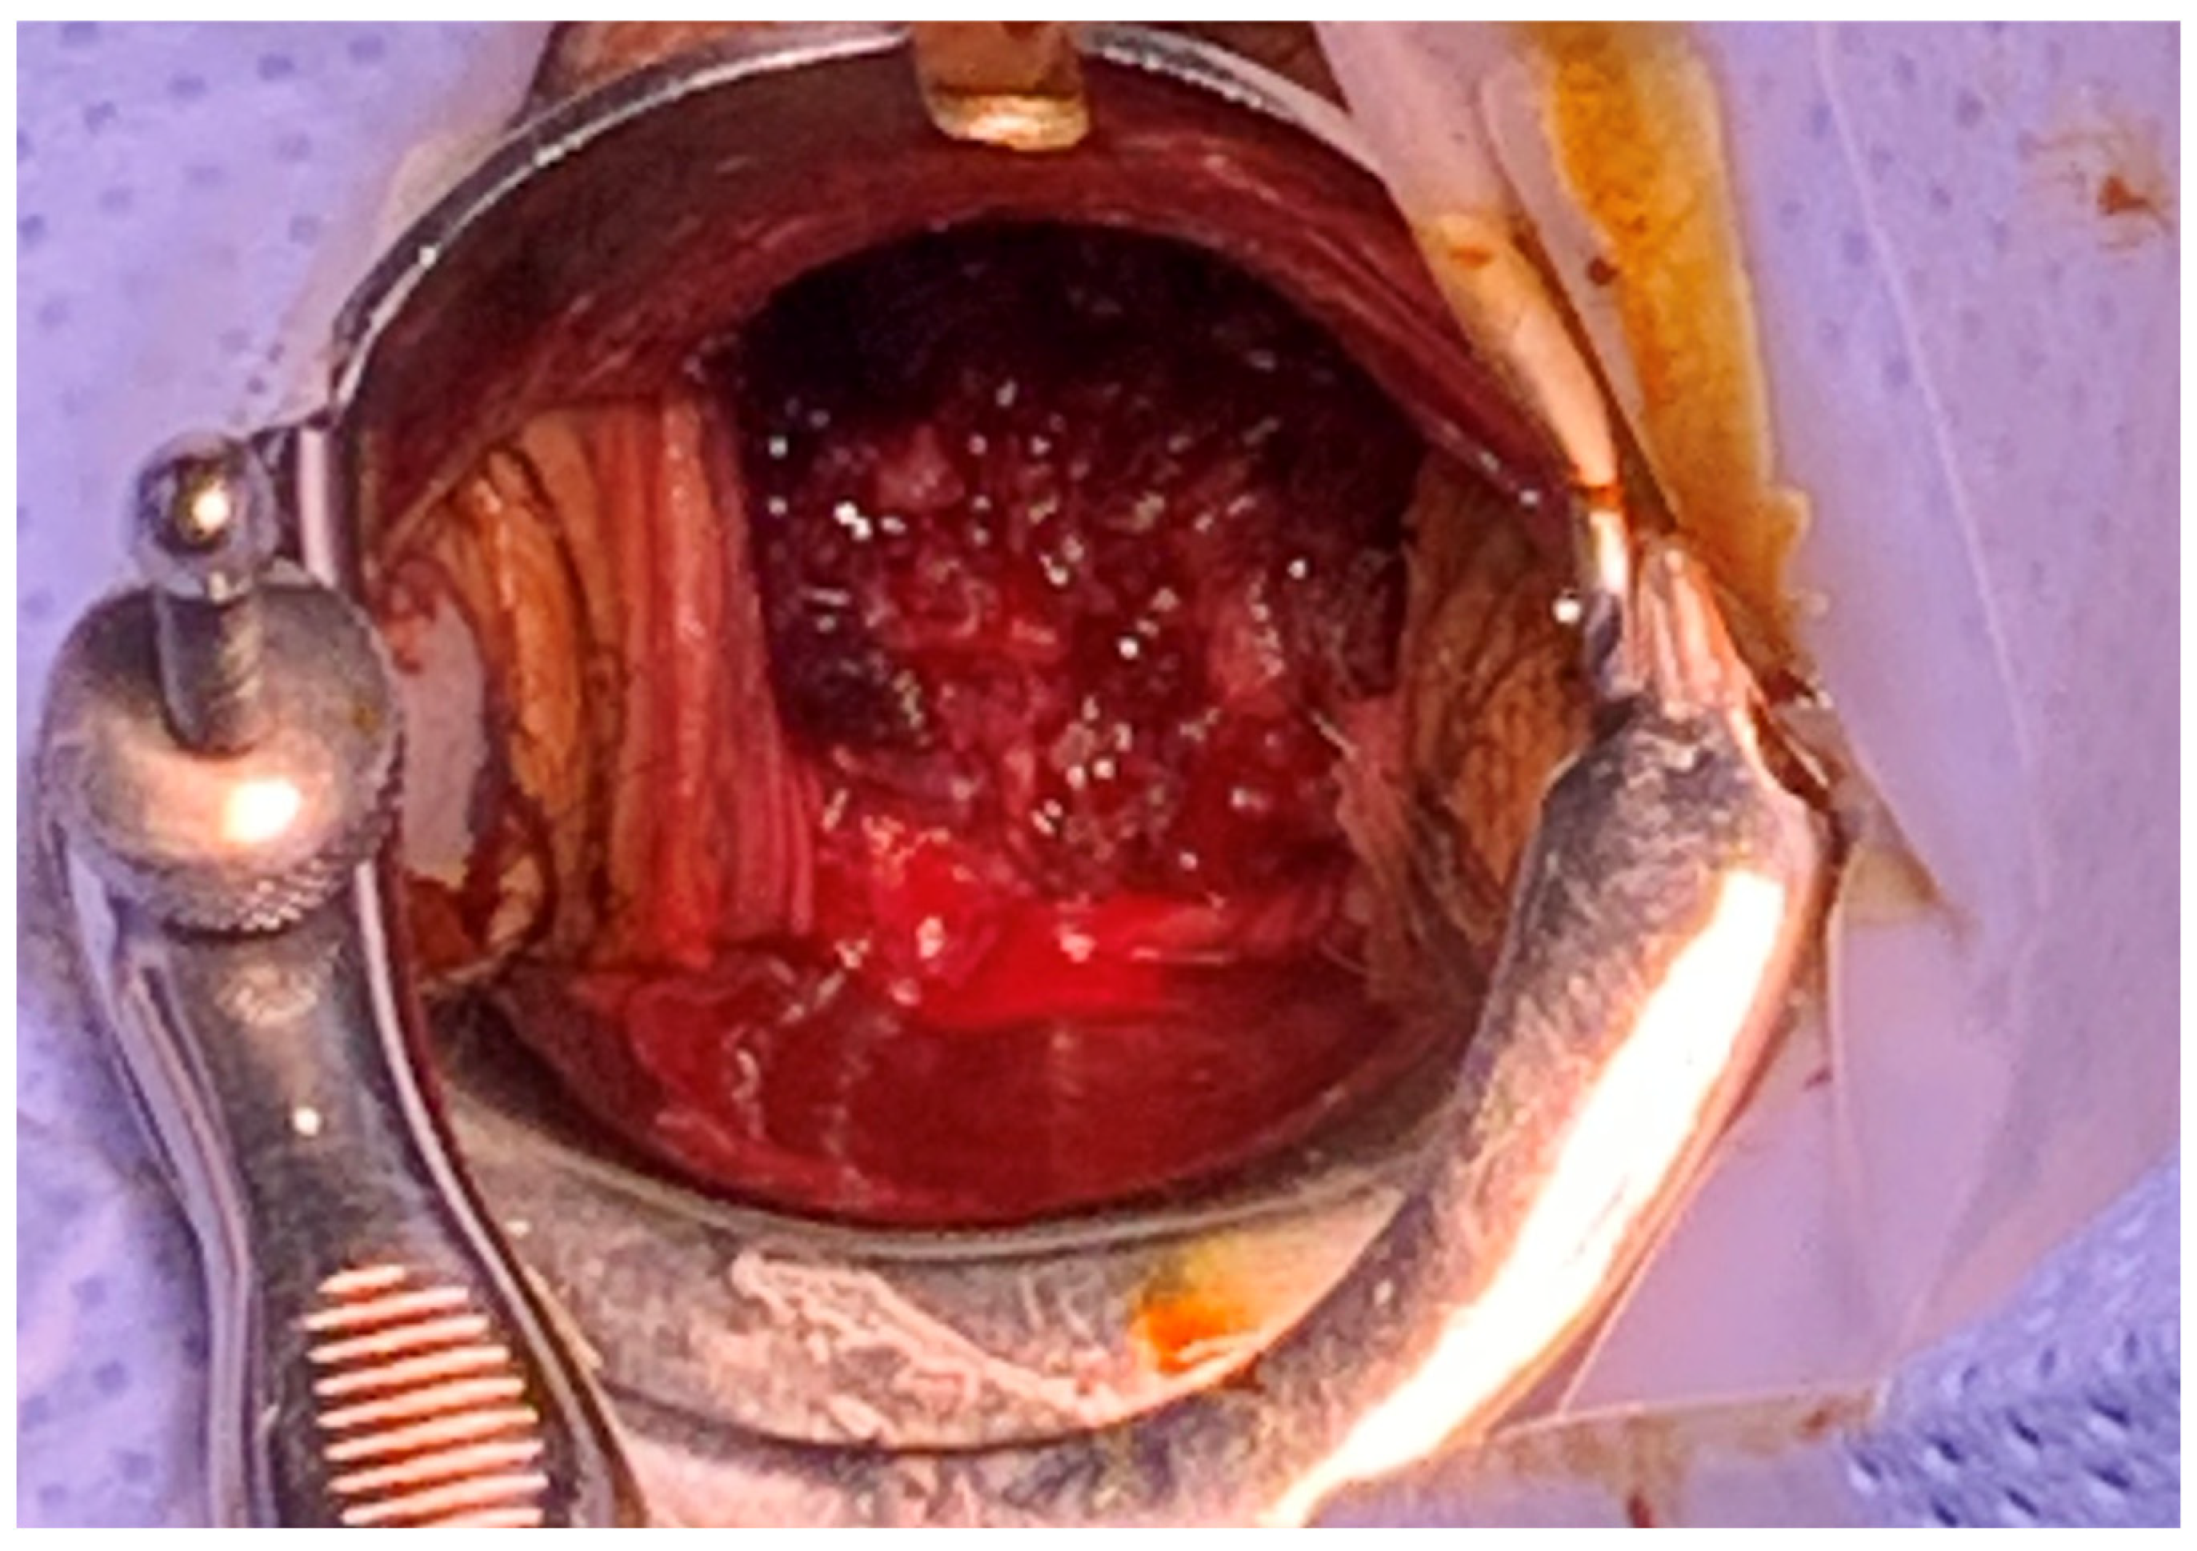

On vaginal examination, a solid mass-like lesion with an irregular surface was visible along with active bleeding (Figure 1). The uterine cervix appeared abnormal upon examination. Following transvaginal ultrasound, abnormal uterine characteristics were observed, but the bilateral ovaries were well-defined. Following computed tomography, a definite sign of uterine inversion was suspected, without demonstrable vaginal tumors. Immediately following the diagnosis of non-puerperal uterine inversion, Johnson’s maneuver was attempted to perform uterine reversion at bedside. However, despite several attempts at manual replacement, no relaxation or mobility was obtained when traction was applied. The extent of vaginal bleeding had not been reduced at all, and hypotension was not recovered quickly even after extensive transfusion and the provision of massive fluid supply. Further treatment with surgical management was warranted to explore the severity of the inversion and determine a method of reducing the patient’s vaginal bleeding.

Figure 1. Initial vaginal examination. A solid mass-like lesion was visible along with active bleeding.